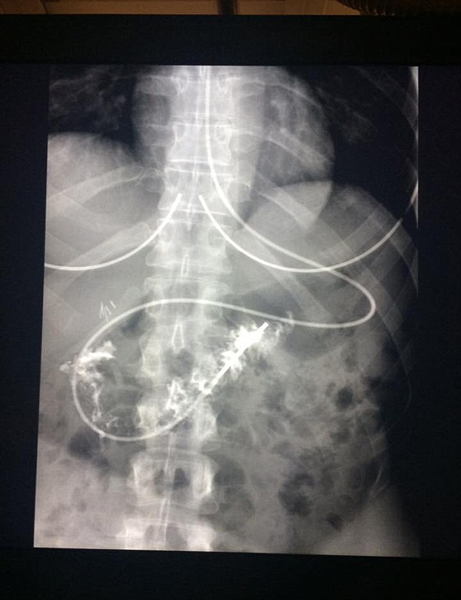

据了解,胃轻瘫的患病几率极小,只有35万分之一。这种病破坏了查曼从大脑到胃部的消化道神经,导致她从喉咙到肠道的消化道瘫痪,无法消化食物,吃一片面包就足以呕吐好几天。所以她只能通过一条长约2米的导管穿过鼻子,每天24小时为身体输送营养液。食物摆在眼前却要忍受饥饿,她的体重曾在9天内骤降了20公斤。由于随时可能会呕吐,她不得不断绝了自己的社交活动。